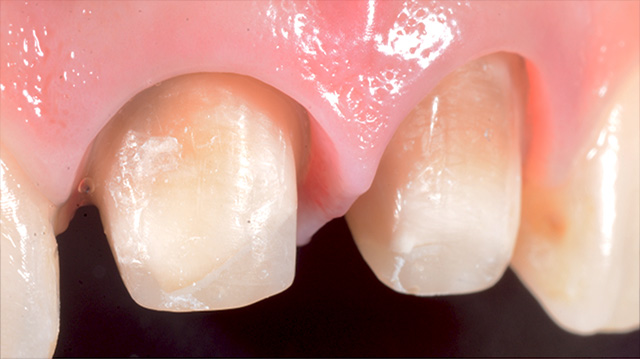

| 年代・性別 | 40代 男性 |

|---|---|

| 主訴 | 前歯の被せ物が取れた |

| 治療回数 | 3回 |

| 治療期間 | 約1ヶ月 |

| 費用 | 仮歯 5,500円 ジルコニアクラウン 176,000円 |